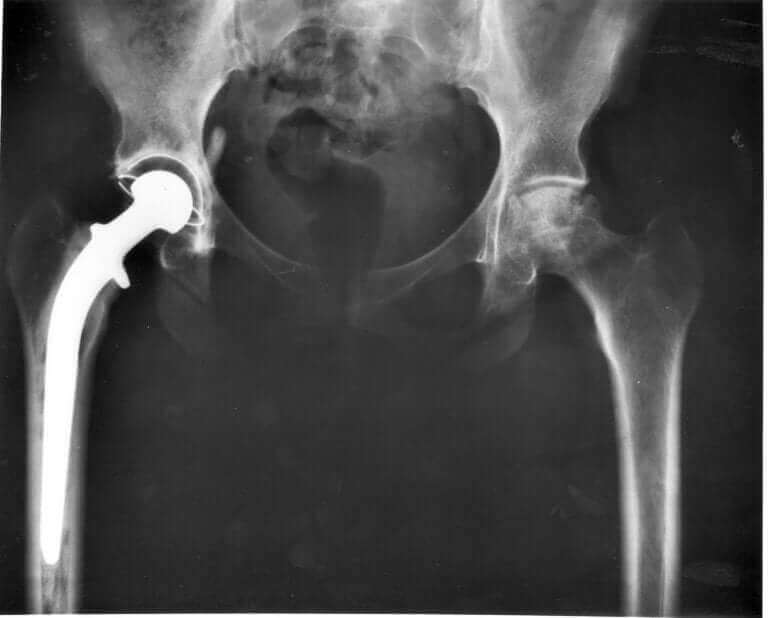

Veterineriniz, kedinizin kalça eklemlerine bakmak ve kesin sorunu belirlemek için pelvik röntgen çekmek zorunda kalacak. Aslında, kedinizin kalça displazisi varsa, rahatlatması ve semptomları yavaşlatması için bazı tedaviler bulunmaktadır. Ne yazık ki hastalığı ortadan kaldırmak için hala bir tedavisi mevcut değildir.

Bu tedavilerin bazıları, fizik tedavi, bazı aktiviteleri kısıtlama, anti-enflamatuar ilaçlar (oral veya enjekte) ve kilo takibini içerir. Daha ciddi vakalarda kalça protezi ameliyatı gerekebilir.